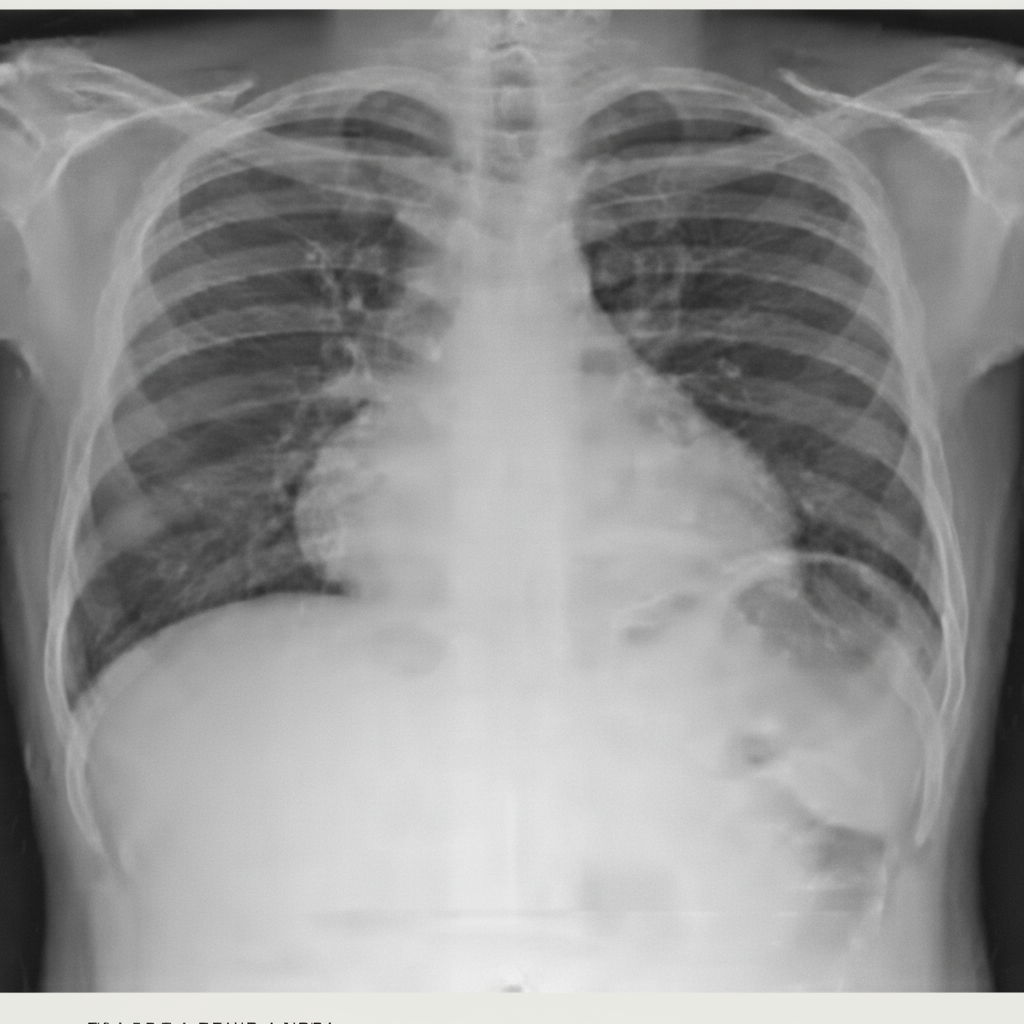

Explanation: ***Amiodarone*** - **Amiodarone-induced pulmonary toxicity** is a well-known adverse effect, presenting with bilateral **pulmonary infiltrates** on chest X-ray and progressive dyspnea. - The drug accumulates in **lung tissue** due to its lipophilic nature and long half-life, causing **inflammatory pneumonitis** and potentially **pulmonary fibrosis**. *Digoxin* - Primarily causes **cardiac toxicity** including arrhythmias, heart block, and **digitalis toxicity** symptoms like nausea and visual disturbances. - Does not cause **pulmonary infiltrates** or lung parenchymal damage as its main mechanism involves **Na+/K+-ATPase inhibition**. *Verapamil* - A **calcium channel blocker** that primarily affects the cardiovascular system, causing **bradycardia**, **hypotension**, and potential **heart block**. - **Pulmonary toxicity** is not a recognized adverse effect of verapamil therapy. *Propranolol* - A **non-selective beta-blocker** that can cause **bronchospasm** in asthmatic patients but does not cause **pulmonary infiltrates**. - Main side effects include **bradycardia**, **hypotension**, and **fatigue**, not parenchymal lung disease.